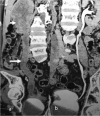

The purpose is to discuss abdominal tuberculosis mimicking malignancy involving the abdominal viscera. TB of the abdominal viscera is common, especially in countries where tuberculosis is endemic and in pockets of non-endemic countries. Diagnosis is challenging as clinical presentations are often non-specific. Tissue sampling may be necessary for definitive diagnosis. Awareness of the early and late disease imaging appearances of abdominal tuberculosis involving the viscera that can mimic malignancy can aid detecting TB, providing a differential diagnosis, assessing extent of spread, guiding biopsy, and evaluating response.